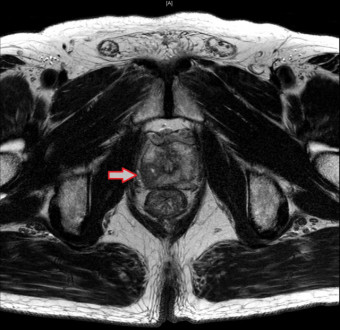

- 영상 검사: 초음파, MRI, CT 스캔 등을 통해 전립선의 상태와 암의 퍼진 정도를 확인합니다.